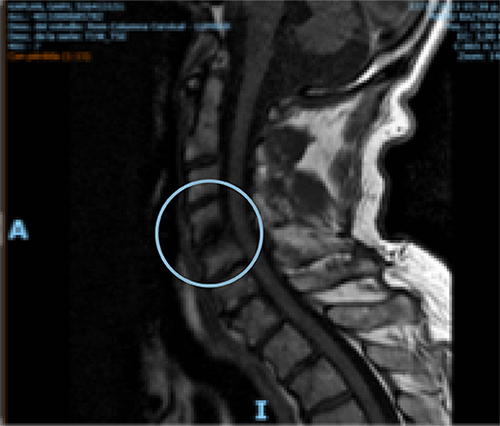

Comparative MRI of cervical spine pre- and one-year post-treatment in a 70-year-old man diagnosed with osteoarthritis of the cervical spine. The red arrow shows the remodeling of the affected disc.

PRE-TREATMENT

POST-TREATMENT